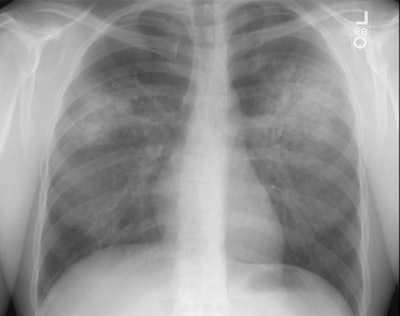

Wegeners overlap syndrome with extensive pulmonary hemorrhage: The patient shown in the image below had an extensive travel history and his parents were missionaries in New Guinea. He was referred to the rheumatology service for complaints of polyarthralgia. On exam, additional history revealed complaints of epistaxis, and later hemoptysis. CXR was obtained and demonstrated bilateral consolidations which were primarily confined to the superior segments of the lower lobes and posterior upper lobe segments. A PPD was placed and was negative, and the patient was HIV negative. Although plain films of the paranasal sinuses were normal, on direct visualization, mucosal ulcerations were identified. At bronchoscopy, blood was noted within the airways- indicating that the parenchymal abnormalities were likely the result of hemorrhage. Both serum and BAL fluid were C-ANCA positive and a diagnosis of Wegener's was made. However, the open lung biopsy specimen demonstrated both features of Wegener's and an eosinophoilic vasculitis (Churg-Strauss) and the final diagnosis was that of an overlap vasculitis. The patient was treated with steroids and methotrexate with a rapid clearing of the parenchymal abnormalities. |

Patchy focal or diffuse parenchymal consolidations and ground

glass opacities are found in 30-53% of cases and are usually due

to pulmonary hemorrhage. The opacities are generally random

or patchy in distribution [14], but bilateral perihilar and

peribronchovascular distributions are the most common [15]. The

infiltrates may be found to be cavitary by computed tomography.

Diffuse alveolar hemorrhage occurs in about 10% of patients

producing a diffuse ground-glass opacity that often spares the

subpleural lung [12,13].